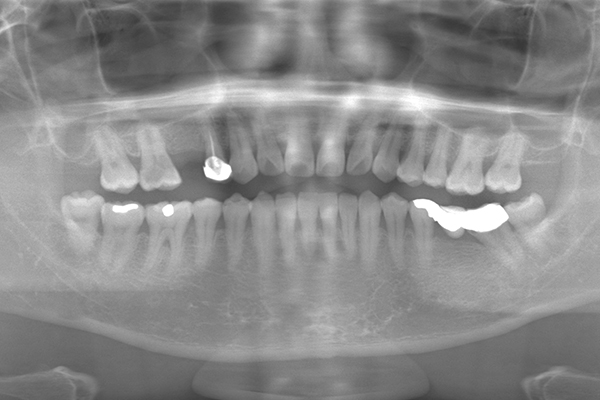

治療前〜治療後のレントゲン写真

患者様の要望過去に治療したブリッジを外し咬み合わせの平面を整えて、被せ物や詰め物を綺麗にしたい。

治療期間10ヶ月

治療費用1,600,000円

治療内容インプラント2本、アンカースクリューを用いた部分矯正、

セラミックによる補綴治療

治療のリスクセラミックの破折の可能性